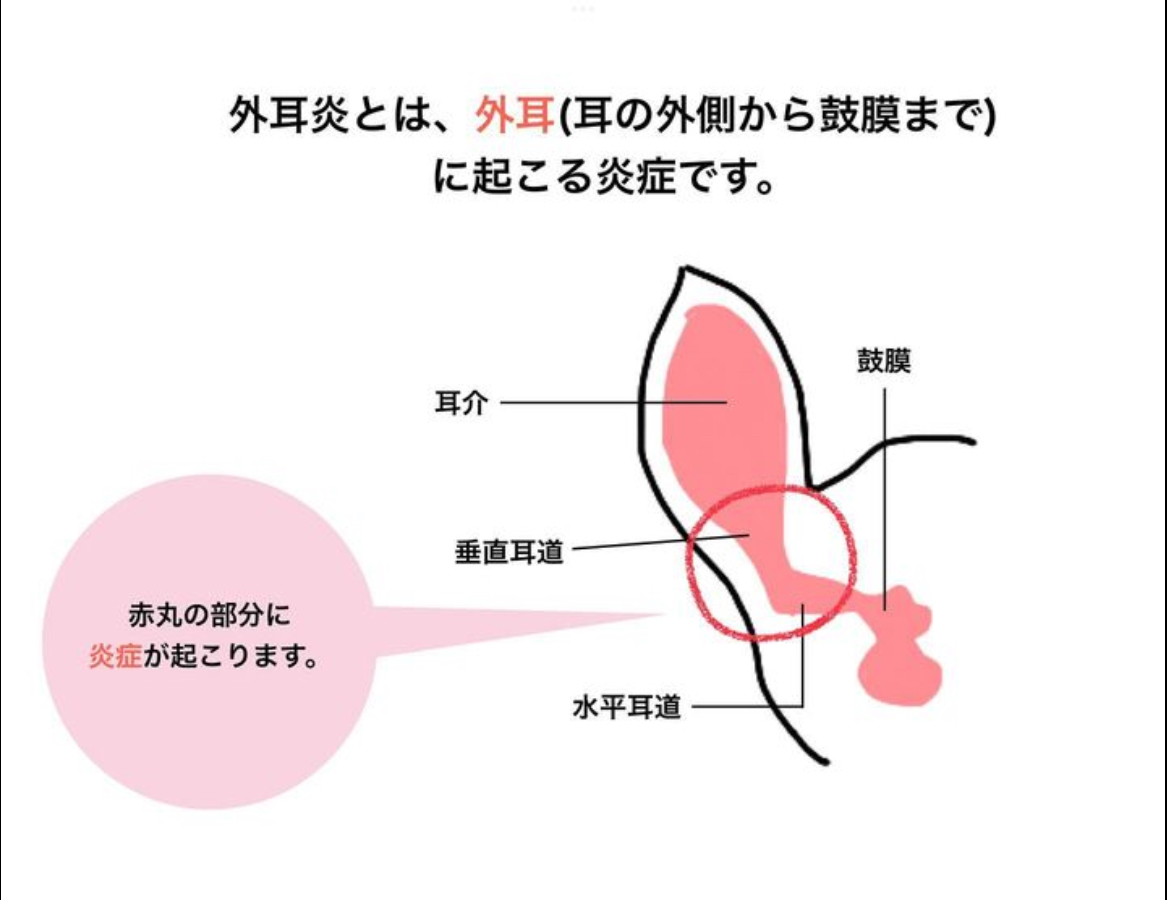

2023.11.10外耳炎

外耳炎👂 外耳炎とは… 耳の外側から鼓膜までに炎症が起こることです。 治療法💊 ●常在菌のマラセチアが増えている場合は… ・オスルニア点耳薬→…